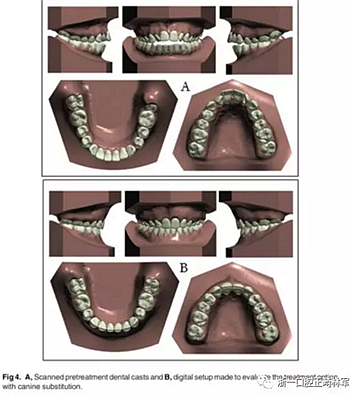

經(jīng)過考慮,選擇方案1拔除上頜側(cè)切牙和下頜第二前磨牙。由于早期牙髓壞死,這些根部的牙本質(zhì)很薄,因此在正畸運動過程中上頜側(cè)切牙極易發(fā)生牙根外吸收。同時設(shè)計上頜尖牙的側(cè)向移動。為了改善診斷方案和治療結(jié)果,考慮到拔牙方式的獨特性,我們對此病例進行了數(shù)字化設(shè)置(圖4)。